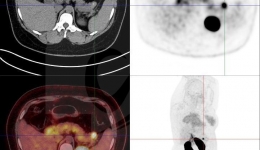

• 罕见!频发严重低血糖,竟是因为胸部这个包块!

罕见!频发严重低血糖,竟是因为胸部这个包块!

今年4月,一名来自西藏地区的54岁男性患者,因为“反复昏睡、抽搐、大汗7月,加重1月”入院。7个月以来,患者反复出现昏睡、意识不清、肌肉抽搐、四肢僵硬,伴大汗、不自觉吼叫。到当地医院住院时监测昏睡中血糖仅有1~2mmol/L,脑CT未见明显异常,...